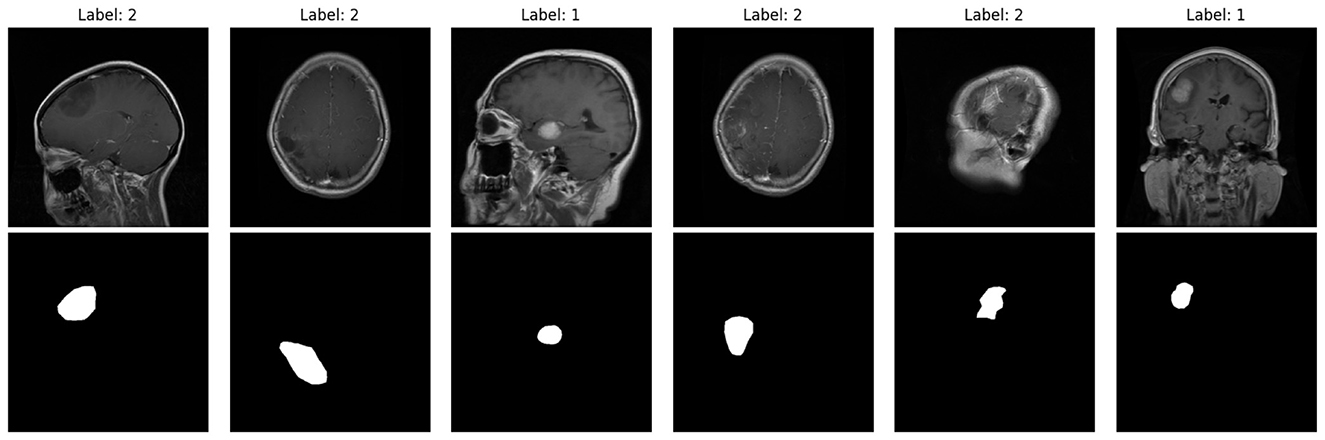

As part of the preprocessing stage, binary tumor masks assist in confirming the spatial correspondence between the tumor and the respective annotated bounding box. These are the examples presented in Figure 3. The top row contains raw MRI slices, whereas the bottom row contains the respective masks. These masks serve the purpose of assuring the proper placement of bounding boxes around tumor margins before the training stage.

Figure 3

Example MRI slices (top) with corresponding tumor masks (bottom) from the Figshare dataset, used to validate tumor regions before bounding-box annotation.